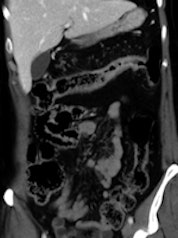

Acute ileal involvement by Crohn's disease, with wall thickening and mucosal enhancement.

Many other gastroenterological pathologies require imaging for detection and evaluation. Ultrasonography is the first step when liver, pancreatic, or biliary disease is suspected. In inflammatory bowel diseases, CT and more recently MRI have proved to be valuable tools for detecting and staging the disease, as well as for monitoring treatment.